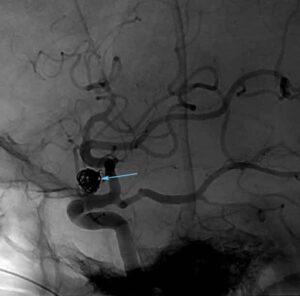

Radiologia interventistica: aumentano gli interventi che sostituiscono il bisturi

Le sale operatorie stanno dicendo sempre piu' addio al bisturi, in favore di stent, sonde e 'palloncini' in grado di...